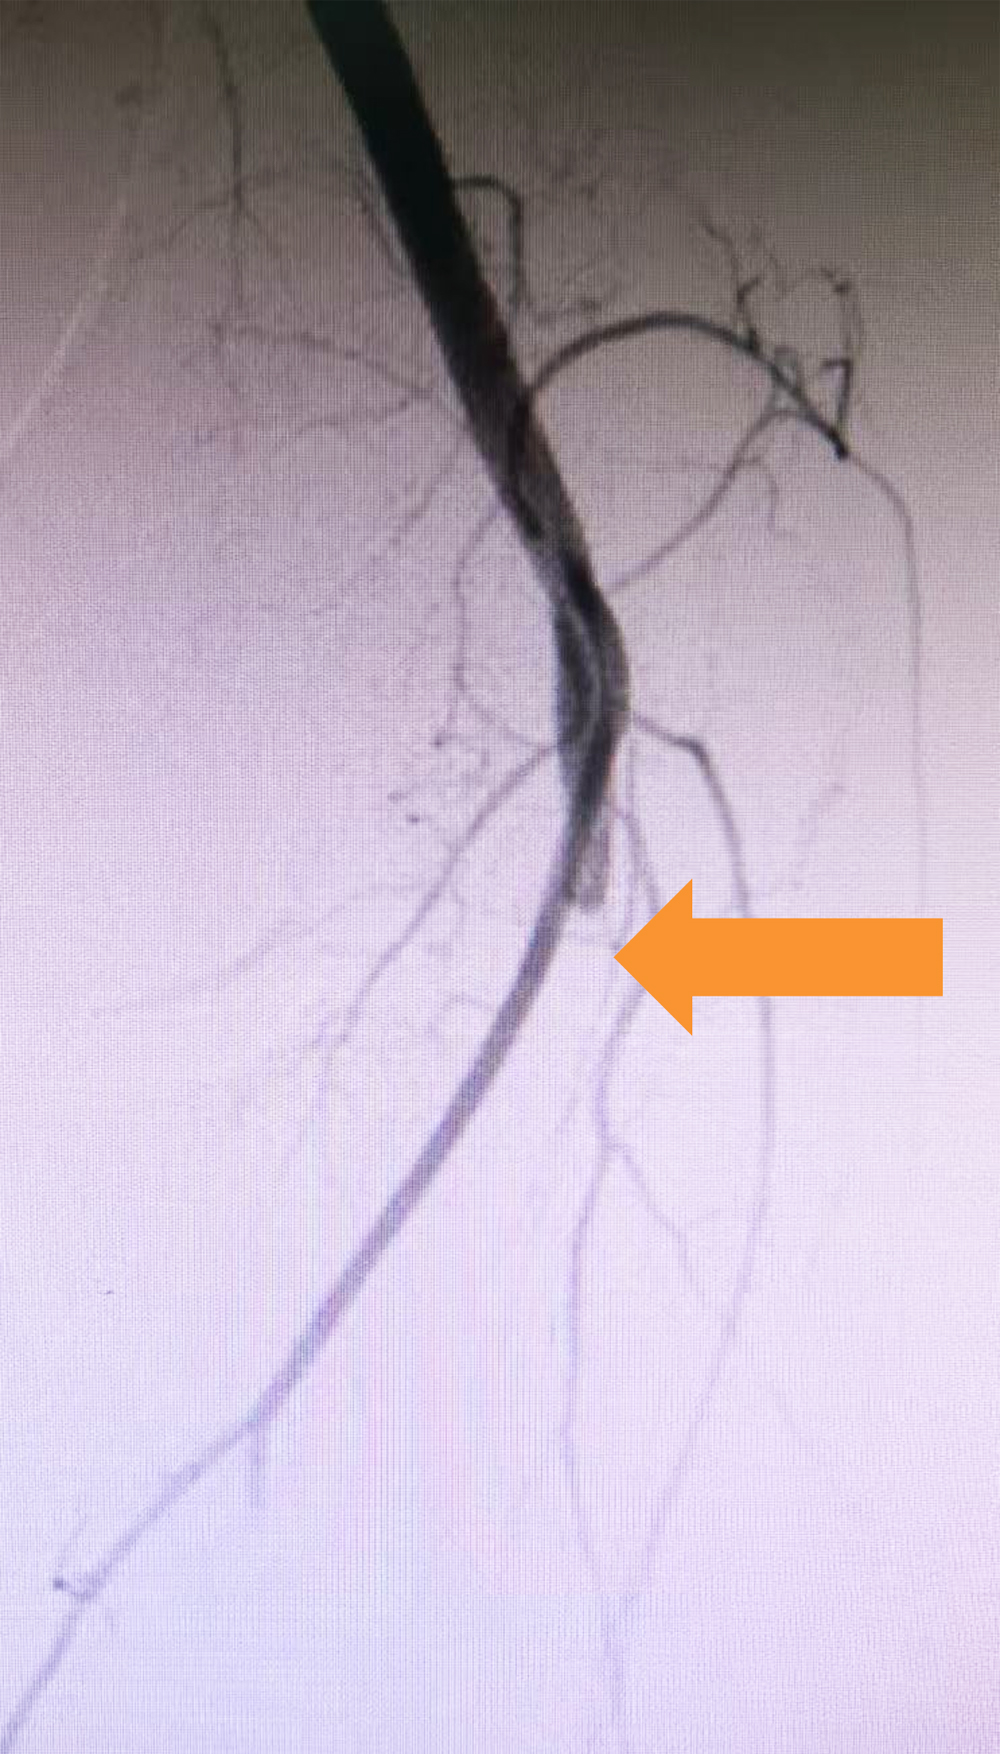

取栓前 左下肢动脉造影,显示膝下动脉栓塞,远端无血流